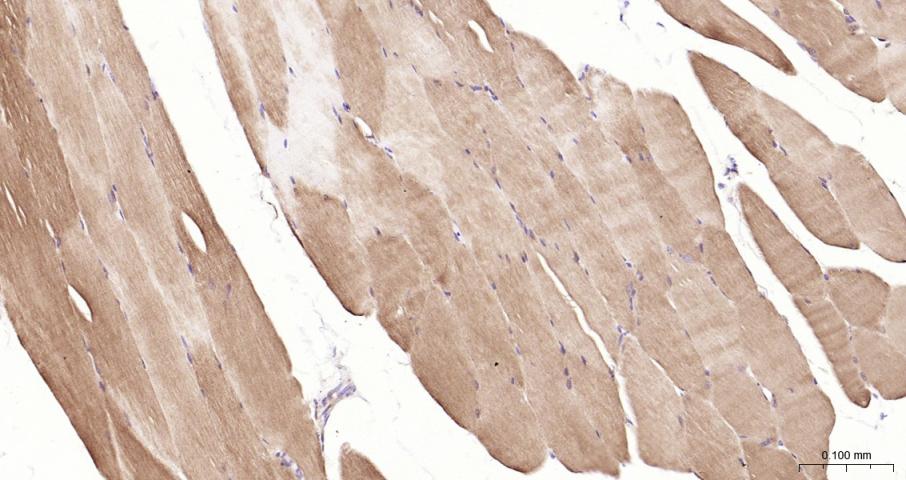

Paraformaldehyde-fixed, paraffin embedded Mouse Skeletal muscle; Antigen retrieval by boiling in sodium citrate buffer (pH6.0) for 15 min; Antibody incubation with LDHA Monoclonal Antibody, Unconjugated(bsm-62875R) at 1:200 overnight at 4°C, followed by conjugation to the bs-0295G-HRP and DAB (C-0010) staining.

Paraformaldehyde-fixed, paraffin embedded Rat Skeletal muscle; Antigen retrieval by boiling in sodium citrate buffer (pH6.0) for 15 min; Antibody incubation with LDHA Monoclonal Antibody, Unconjugated(bsm-62875R) at 1:200 overnight at 4°C, followed by conjugation to the bs-0295G-HRP and DAB (C-0010) staining.